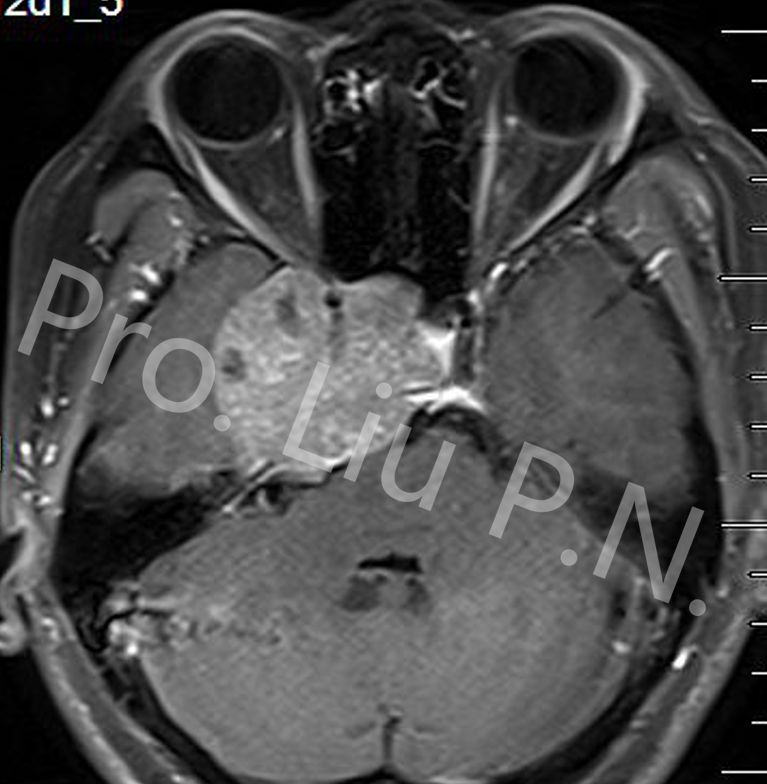

十、经筛-翼突入路手术案例

--左海绵窦神经鞘瘤

![]()